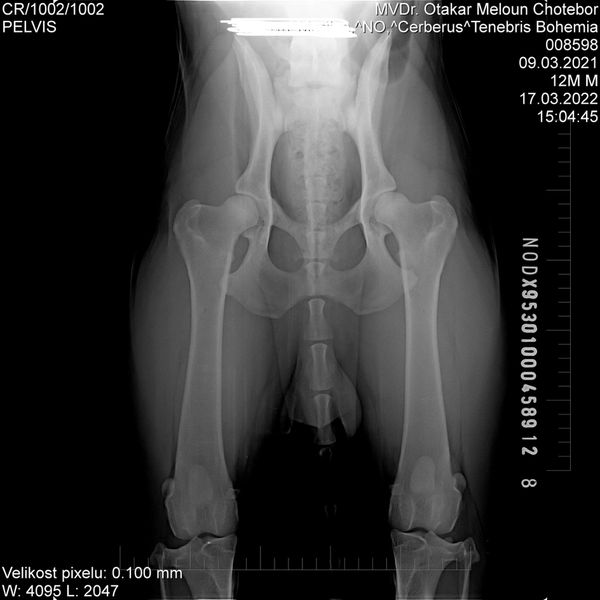

HD: A

ED: 0/0

Spondy: Free